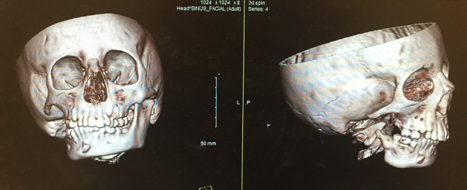

This patient has Pruzansky Grade III hemfiacial microsomia with a missing mandibular body, ramus, and condyle. There is also incomplete formation of the zygomatic arch (cheek bone) and maxillary hypoplasia.